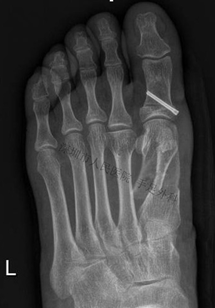

图11:患者拇外翻畸形,籽骨部位行走时疼痛。CT检查显示内侧籽骨较外侧明显增大(箭头),考虑为拇外翻合并籽骨炎。I期行拇外翻矫形+籽骨清理术,术后疼痛缓解,6个月后再次出现行走疼痛

图12:CT检查显示内侧籽骨增生,关节面不平整(箭头)

图13:术中定位内侧籽骨(左图),并切除籽骨(右图,箭头)

图14:术中见籽骨增大,关节面不平整,软骨部分缺损。患者切除籽骨后,经随访疼痛完全缓解

总结:拇趾籽骨炎容易被误诊,特别是拇外翻合并籽骨炎。在治疗此类拇外翻时,在矫正畸形的同时,应积极处理籽骨炎。病变较轻者可行籽骨修整、清理术;对于籽骨退变严重的患者,可行内侧籽骨摘除术。